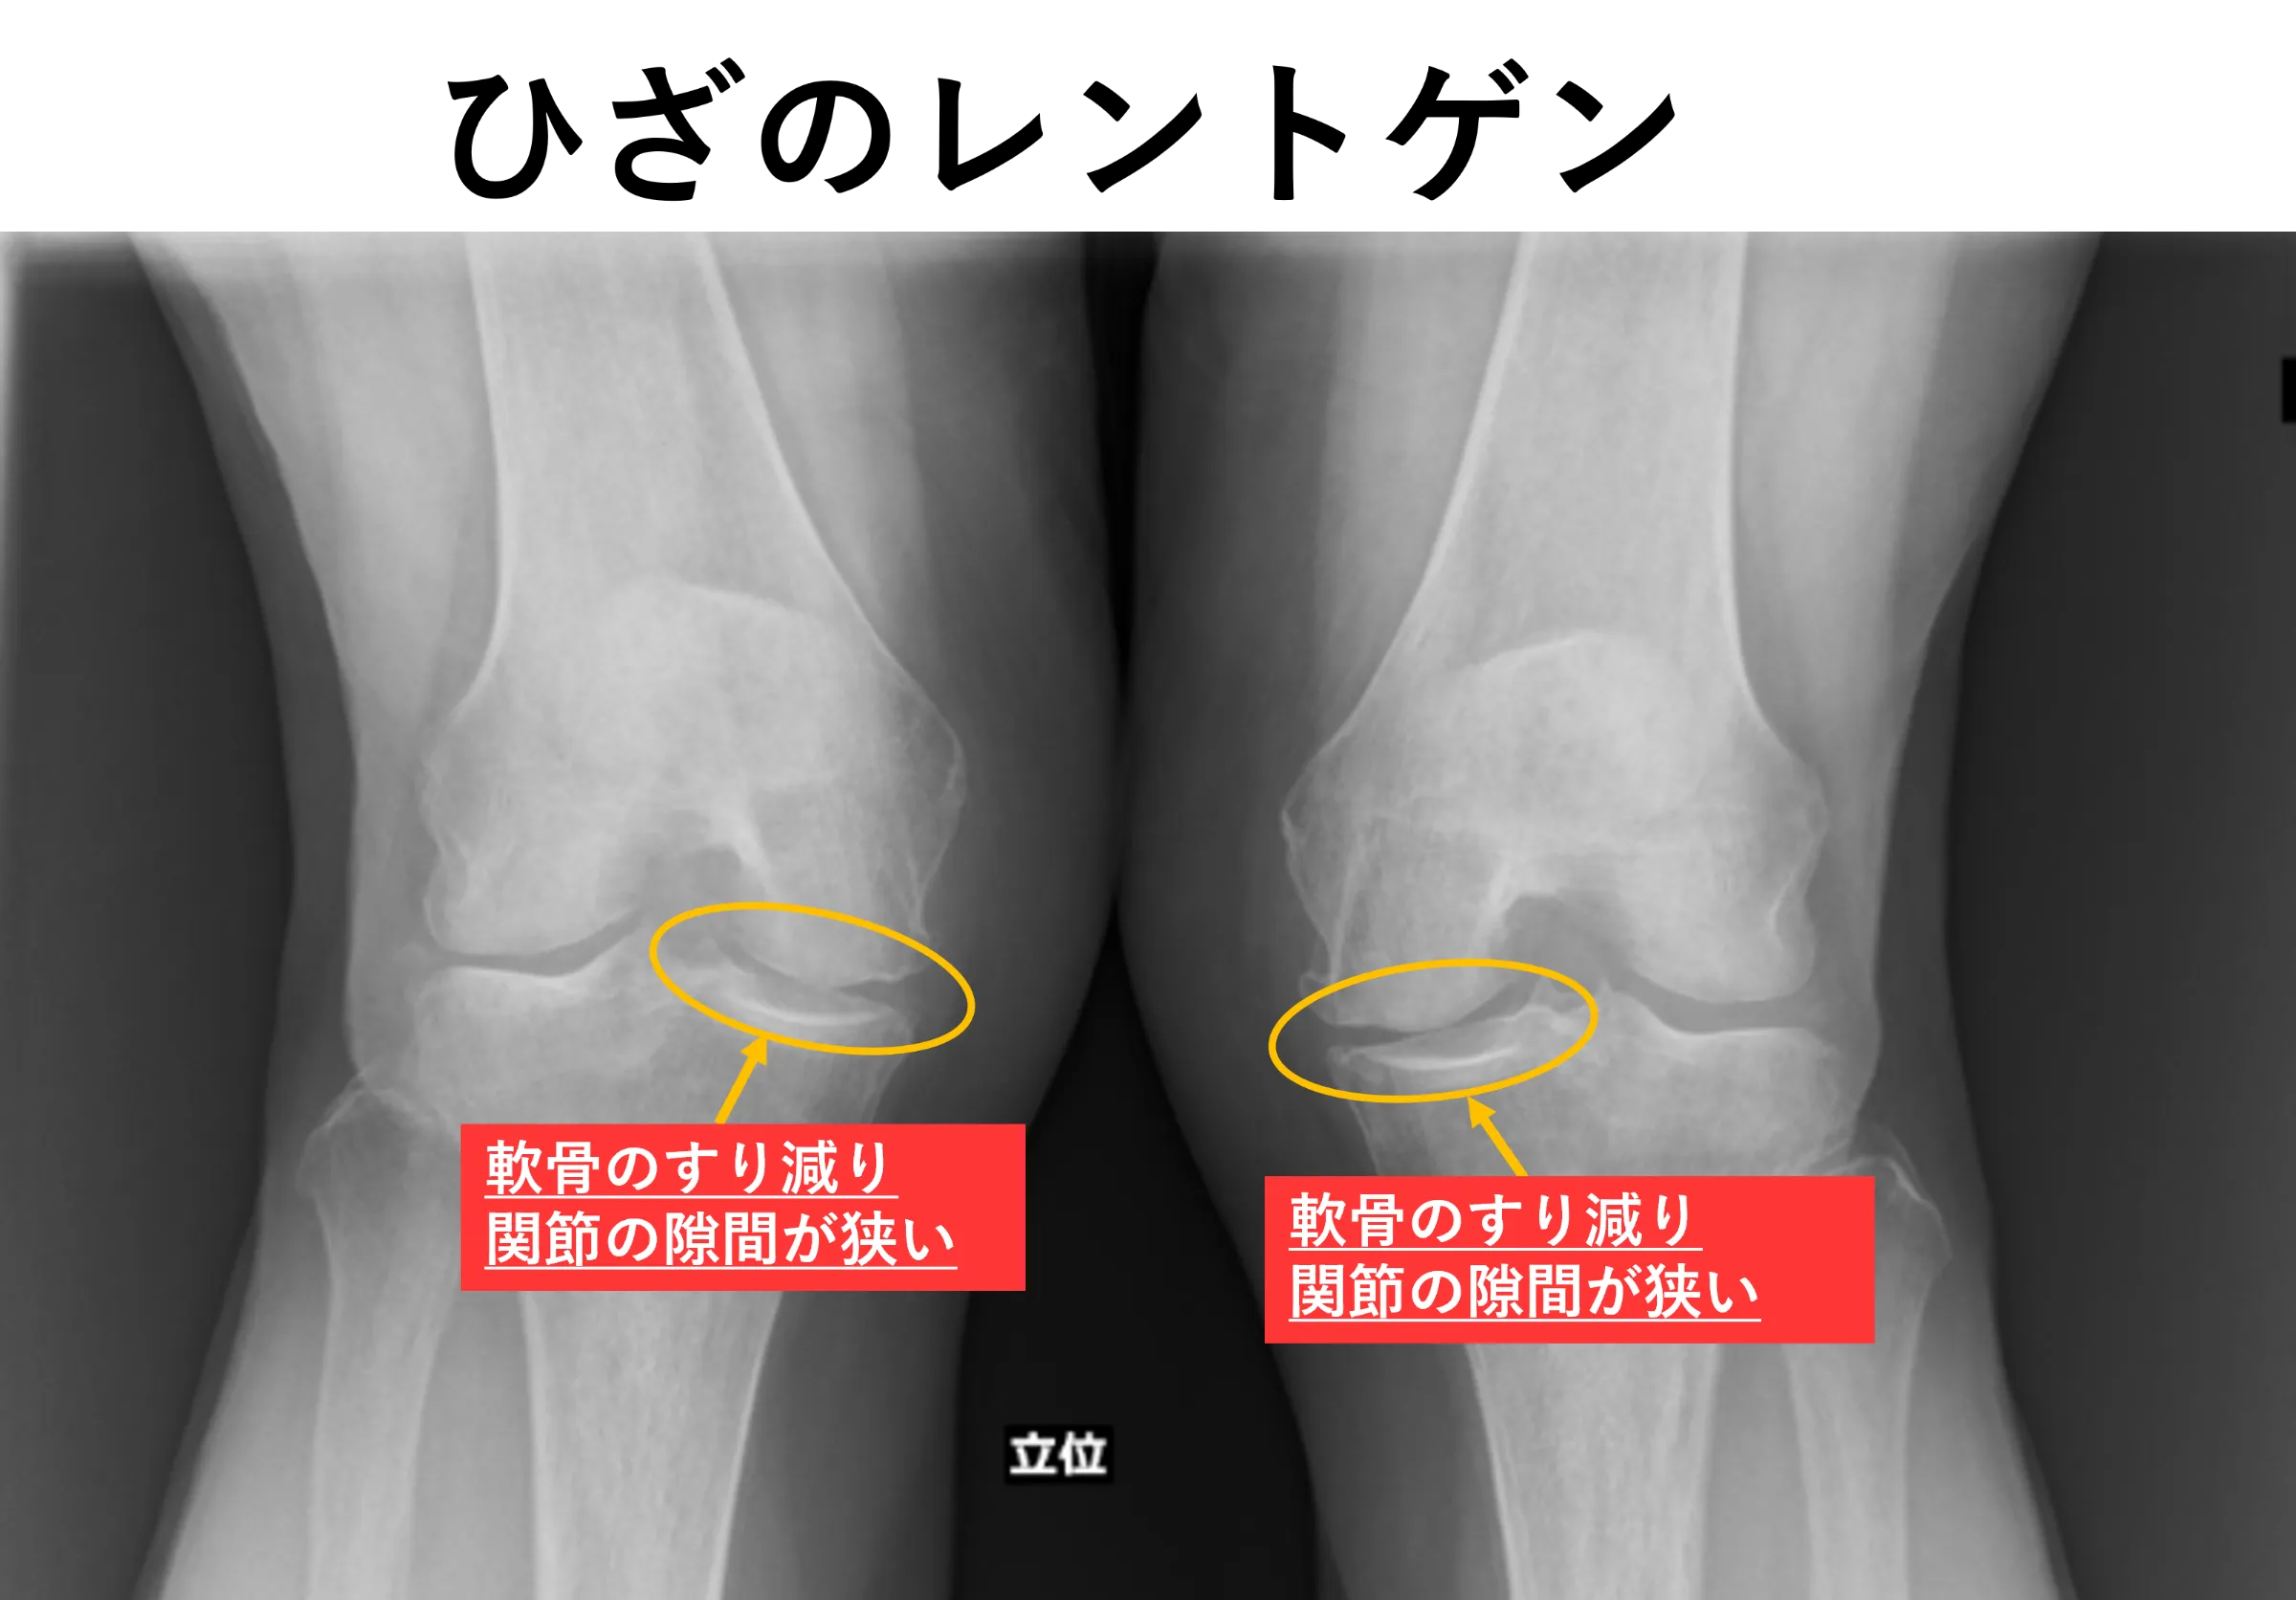

両変形性膝関節症、右変形性股関節症

MRI所見で右変形性股関節症、両変形性肩関節症を認めました。